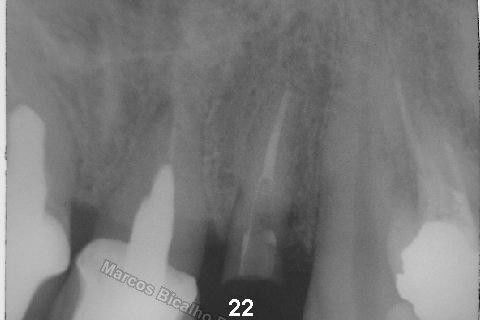

Este caso tem o objetivo de demonstração da técnica que normalmente sigo ; em casos onde ocorre fratura da raiz e consequentemente abscessos, com ou sem formação de fístula. Neste caso fiz a exodontia com preenchimento do alvéolo com biomaterial (osso bovino liofilizado + coágulo do paciente). Após 90 dias, mais ou menos, instalei o implante. Esperei mais 4 meses e realizei ontem (12/11/2010) a instalação do cicatrizador com o cuidado de preservar tecido mole, sem remoção de material, apenas afastando gengiva e "enrolando" a sobra de mucosa em direção a face vestibular, para promover conservação de papila futuramente. Se ocorrer excesso de papila, sem problema, remove-se um pouco, mas a intenção é não deixar faltar, o que resultaria em indicação para enxertos gengivais.